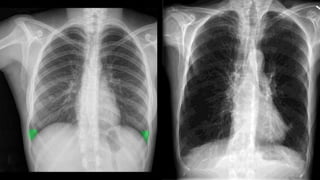

DIAGNOSTIC EVALUATION

• ABG analysis- to assess baseline oxygenation and gas exchange

• CT scan- not done routinely, by may help in differential diagnosis